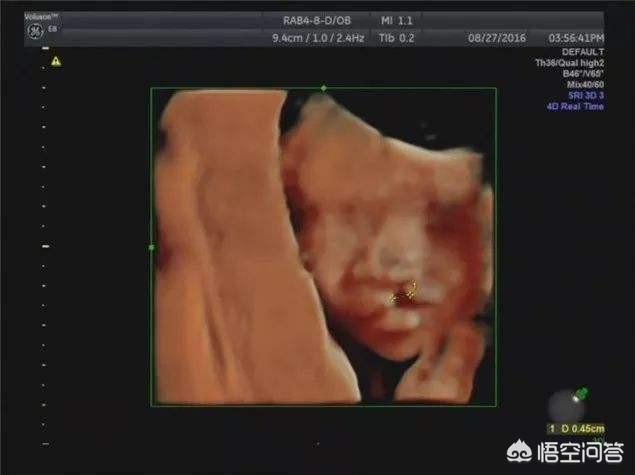

Der 4D-Ultraschall ist eine verbesserte Version des B-Scan-Ultraschalls, mit dem fetale Fehlbildungen, fetale Gesichts- und Körperorgane, Fehlbildungen der Gliedmaßen, wie z. B.: fetale Lippenspalte, Syndaktylie, vierfache Herzkammern, viszerale Ektopie,... erkannt werden können.

Ein 4D-Ultraschall während der Schwangerschaft kann den Fötus auf angeborene Herzfehler, Hydrocephalus, Lippen- und Gaumenspalten und die Entwicklung der Gliedmaßen untersuchen. Der 4D-Ultraschall kann auch das bewegte Bild des Fötus im Körper der Mutter zeigen.

Bei der auch als 3D-Ultraschall oder 4D-Ultraschall bezeichneten Untersuchung handelt es sich um eine Ultraschalluntersuchung, mit der das Vorhandensein von angeborenen Krankheiten in den verschiedenen Systemen und Organen des Fötus ausgeschlossen werden kann.

In vielen Antworten wurde der 4D-Ultraschall erwähnt, eine der in den letzten Jahren immer beliebter werdenden Ultraschallmethoden, die es ermöglicht, das Bild des Fötus noch deutlicher zu sehen, was den werdenden Müttern und Vätern Freude und Vergnügen bereitet, aber auch die Möglichkeit bietet, Videos oder Fotos als Andenken aufzunehmen.